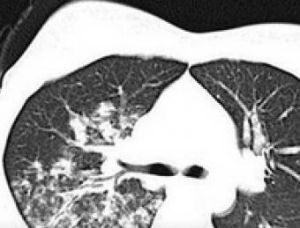

胸部X線表現:支原體肺炎的基本病理表現為支氣管和細支氣管炎及間質性肺炎。胸片表現呈多樣化,無特徵性,可有肺紋理增強及沿紋理分布的多發不規則、密度較低、均勻斑片狀影,半數以上呈多葉分布;近半數兩側被侵犯,大多數病例有下葉受累;病變可孤立地局限在周圍部位,但大多從肺門向肺野伸展且逐漸變淺的扇形陰影;肺部常見一處或多部位的斑點狀。病灶吸收較慢,長者可達4周以上,約1/3患者可出現單側性短暫的胸腔積液。